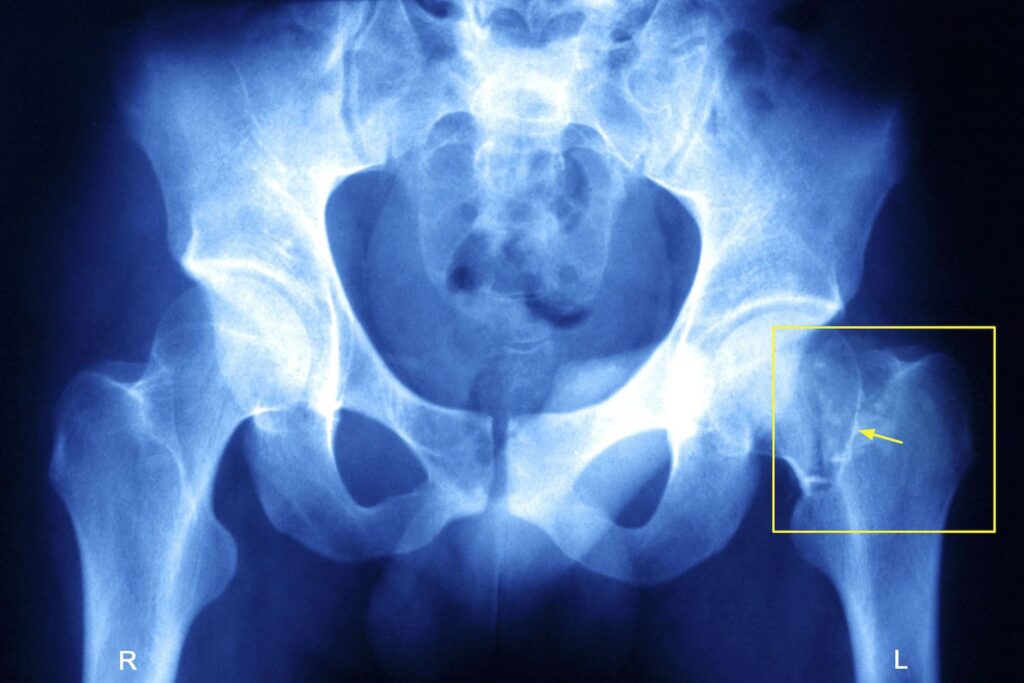

At Melbourne Orthopaedic Clinic, diagnosing a hip fracture begins with a physical examination to assess range of motion, strength, and discomfort. Diagnostic imaging confirms the diagnosis and determines fracture type and location:

• X-rays: The primary imaging method for hip fractures, X-rays reveal the location and severity of the break.